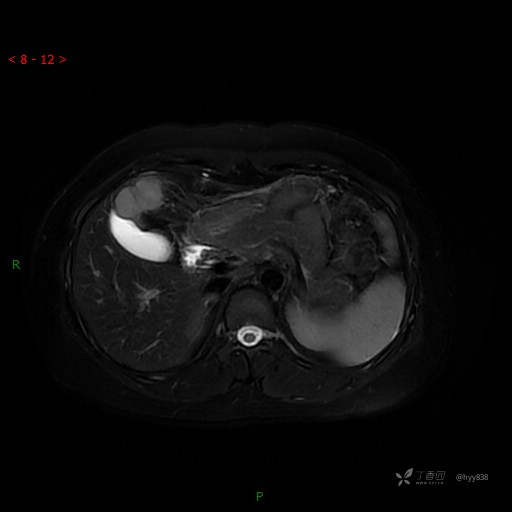

动态增强(动脉早期、动脉晚期、门脉期)